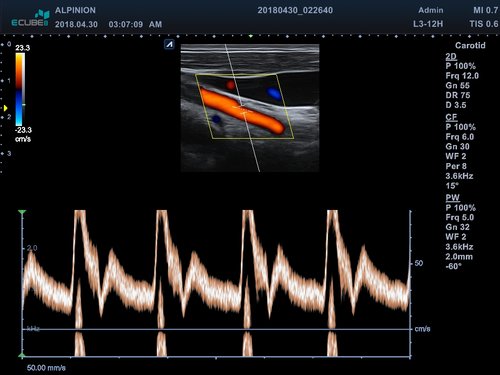

• PW-Doppler (Pulsed-Wave): Verfahren, das ein Geschwindigkeitsspektrum von beweglichem Gewebe und Flüssigkeiten an einer bestimmten Position liefert

• Farbdoppler: farbige Darstellung der Richtung des Blutflusses

• L3-12T (3-12 MHz) für Ultraschalluntersuchungen in Bereichen Brust, Notfallmedizin, MSK, Vaskulär, Kleine Organe, Appendix